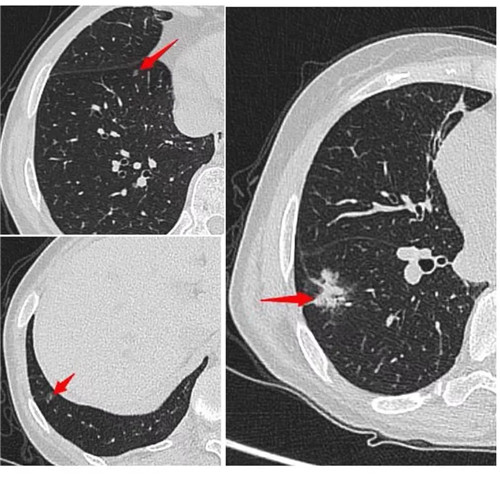

經(jīng)過術(shù)前充分評估,崔凱主任決定一次手術(shù)同期為患者切除雙肺總共六枚結(jié)節(jié)。手術(shù)團隊應(yīng)用minics肺結(jié)節(jié)三維重建分析及術(shù)前CT引導下錨針穿刺定位等先進工具,精準定位患者雙肺的6枚磨玻璃結(jié)節(jié),其中最大的2cm,最小的0.6cm。

術(shù)前各項準備完畢,崔凱主任為患者行“單孔胸腔鏡右肺下葉切除術(shù) 淋巴結(jié)清掃術(shù) 單孔胸腔鏡左肺上葉尖后段切除術(shù) 左肺下葉背段切除術(shù) 淋巴結(jié)清掃術(shù)”,一次手術(shù)成功將患者兩側(cè)肺部6枚結(jié)節(jié)全部切除,術(shù)后病理結(jié)果提示六枚結(jié)節(jié)均為早期肺癌。